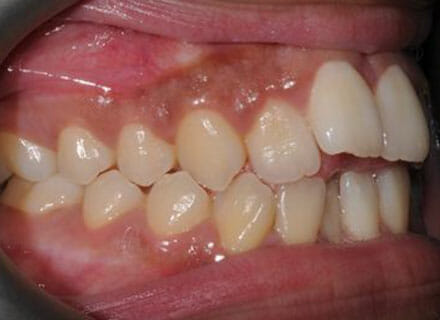

This patient came to us because she hated her smile: it was too narrow, the upper front teeth were all crowded into each other and twisted. She couldn’t eat a sandwich properly with the front teeth because of the gap – the open bite. We were able to expand both jaws to make space to align all the teeth without having to extract – in about 18 months using clear brackets.